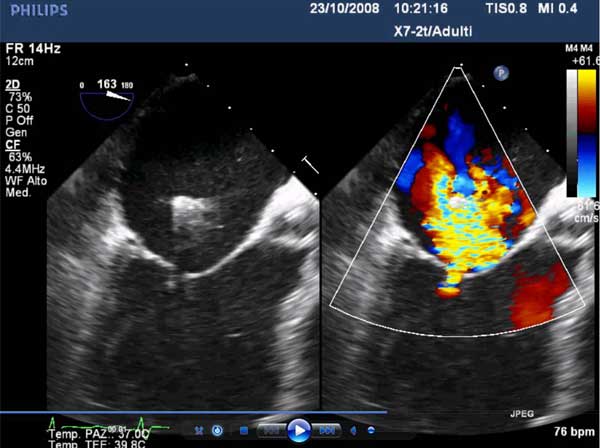

Figure 4

In absence of controlled clinical trial data which are forthcoming from the EVEREST II randomized study, the indications for the MitraClip therapy are currently based on registry experience and will evolve as the technique improves, experience is growing and the data to demonstrate efficacy and safety becomes available. At this time, the best indication for the MitraClip therapy is for symptomatic patients with clinically significant functional or degenerative MR who are at high or increased risk for open heart surgery. From a pure technical standpoint, the procedure so far has only been demonstrated in a subgroup of patients with specific anatomical characteristics which are summarized below and shown in Figure 3. Anatomic suitability is assessed by transesophageal echocardiography, and mitral regurgitation should originate from the central portion of the valve involving the A2-P2 segments, since the device is not ideal to work in the commissures at this time; the mechanism of MR can be either a prolapse/flail or MR due to restricted leaflet motion unrelated to rheumatic disease; the separation between the two leaflets at the site of regurgitation should be limited; severe annular dilatation and/or severe calcification should be absent or is relevant. In case of flail, the flail segment width should be less than 15 mm, and the flail gap less than 10 mm. Figure 4 is a 3D echo image of a patient with posterior leaflet prolapse selected for MitraClip therapy. In case of functional MR, the leaflets should have a minimal residual tissue available for coaptation with the MitraClip device. Figure 5 shows 2D color Doppler jet extension over the coaptation line at TEE short axis transgastric view, while Figure 6 shows the tenting area and the coaptation depth of a patient undergoing MitraClip implant.